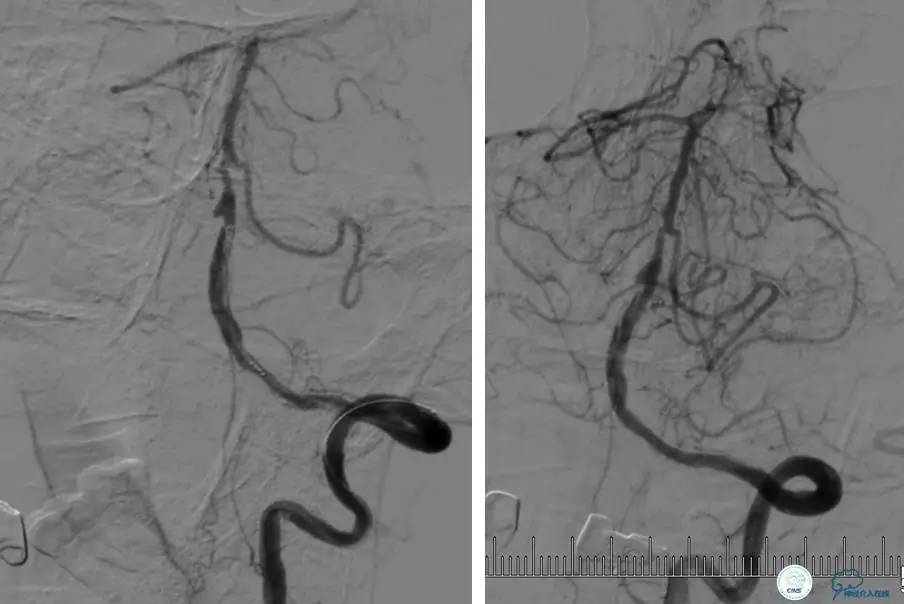

▼DSA示右侧椎动脉发育低下,弥漫性狭窄,可以看到左侧椎动脉反流,因此判断左侧椎动脉V4段CTO。

治疗:

微导丝穿过闭塞段,微导管造影,球扩闭塞段,置入Wingspan支架,血流完全恢复正常。